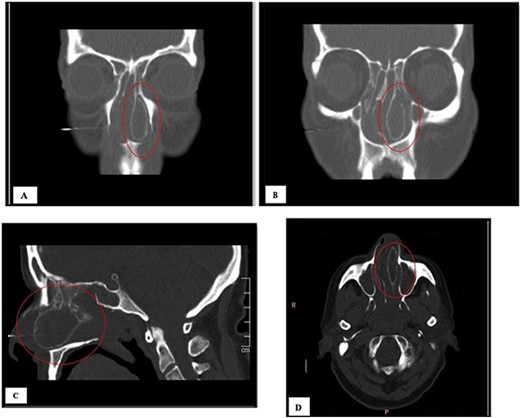

A 64-year-old female presented to our clinic complaining of nasal obstruction more to left side, postnasal discharge, and intermittent headache, anosmia, and facial discomfort since 1 year ago. She had sought previous medical advice and was on intranasal steroid spray and nasal saline irrigation without any improvement, her symptoms affecting the quality of life. She is not known history of allergy; she is not a smoker. She does not have any significant past medical or surgical history. On examination, anterior rhinoscopy showed: left nasal cavity huge mass reaching to left nostril and deviated nasal septum to the right. The endoscopic exam showed huge left-sided nasal mass reaching the level of left nostril, the scope cannot be passed to left-sided nasal cavity, right-sided endoscopic examination showed deviated nasal septum, discharge was appreciated from right middle meatus and along with edematous middle meatus. The nasopharyngeal examination showed post-nasal discharge over the wall without any mass. Rest of complete ears, throat, neck, and cranial nerves examinations were normal. The patient underwent head and paranasal sinus computed tomography (CT) scan, and it shows that this giant CB was pushing the septum to right, as well obstructing sinuses regular drainage contributing to the chronic sinusitis symptoms (Fig. 1). The patient was admitted to hospital for functional endoscopic sinus surgery, left CB release, excision, and septoplasty (Fig. 2). The specimen was collected in a formalin and send to further evaluation and came confirming the diagnosis with “polypoid fragment of respiratory mucosa with cystic space and inflammation,” and it was negative for any malignancy. No perioperative or postoperative complications were seen. The post-operative period showed excellent improvement in patient symptoms. Her quality of life much improved, she is on regular follow up in the clinic along regular nasal endoscopic examination with no evidence of disease recurrence till 12 months post-surgical intervention.

The giant concha bullosa after resection, which was obstructing the left nasal cavity.